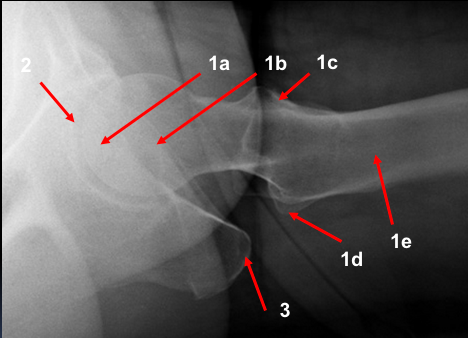

A 78 year old woman fell in her home. She could not get up again due to pain in her right groin. An ambulance was called.

An 48 year old man presented to the ED with 3-day history of left hip pain after falling in the shower. He was struggling to walk. On examination his left leg was a little shorter than the right and slightly laterally rotated.

What action would you take? Justify your course of action / investigation / management!